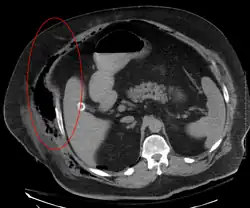

Computed tomography (CT)

Necrotizing fasciitis producing gas in the soft tissues as seen on CT scan

If available, computed tomography (CT) is the most convenient tool in diagnosing NF due to its speed and resolution (detects about 80% of NF cases).[16] CT scan may show fascial thickening, edema, or abscess formation.[2][15] CT is able to pick up on gas within tissues better than MRI, but it is not unusual for NF to present without gas on imaging.[15] In addition, CT is helpful in evaluating complications due to NF and finding possible sources of infections.[15] Its use may be limited in pregnant patients and patients with kidney issues.[15]